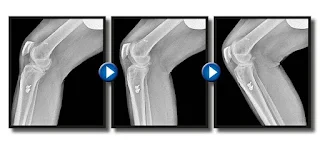

Os avanços tecnológicos começam a permitir que um raio x não tenha apenas uma fotografia, mas se torne uma imagem em movimento, reduzindo custos e procedimentos muito invasivos. Neste sentindo, a Radiografia Digital Dinâmica (DDR) é uma técnica que tem chamado a atenção dos profissionais da saúde por sua capacidade de fornecer imagens detalhadas e em movimento, ampliando significativamente as possibilidades de diagnóstico e tratamento.

A DDR combina recursos presentes nas modalidades de Tomografia Computadorizada (CT) e Ressonância Magnética (RM) para aprimorar o equipamento de raio x. Essa tecnologia permite a obtenção de imagens digitais individuais em alta velocidade, produzindo uma série coordenada de incidências radiográficas, como se fossem fotografias animadas.

A ideia é similar ao de um filme analógico que combina várias fotografias para produzir uma imagem em movimento.A radiografia dinâmica em tempo real proporciona ainda maior precisão e menor exposição à radiação.